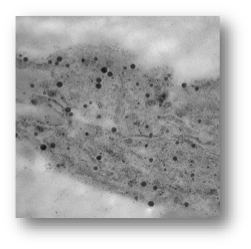

治療前の色素・インク

岩の状態

Qスイッチレーザー治療後

小石の状態(細かく破壊できていない)

ピコレーザー治療後

砂の状態(粒子レベルまで粉砕されている)